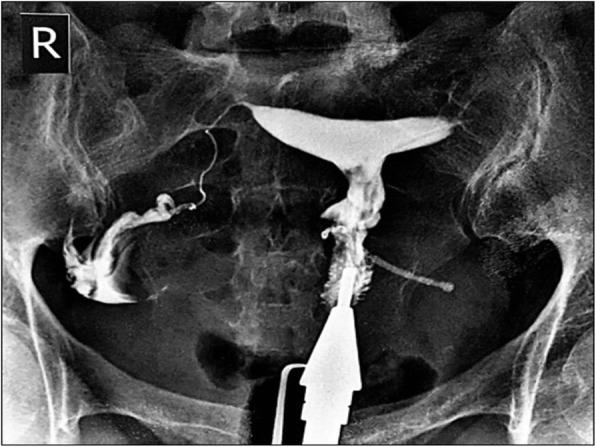

In this study, a case of copper IUD migration through cesarean scar defect is presented, in such a way that was successfully managed by cystoscopic removal. A 31-year-old female with a history of lower urinary symptoms referred to the clinic for her secondary infertility work-up. A copper IUD outside the uterus in the bladder was found using hysterosalpingraphy. A plain abdominal radiography also confirmed the presence of a T-shaped IUD in the pelvis. According to ultrasound, the copper IUD was partly in the bladder lumen and within the bladder wall. The patient had a history of an intrauterine device insertion eight years ago followingher second cesarean delivery. Three years later, her IUD was expelled, and another copper IUD was inserted. Thesecond copper IUD was alsoremoved while she decided to be pregnant. The patient finally underwent a hysteroscopic cystoscopy. The intrauterine device with its short arms embedded in the bladder wall was successfully extracted through the urethra.